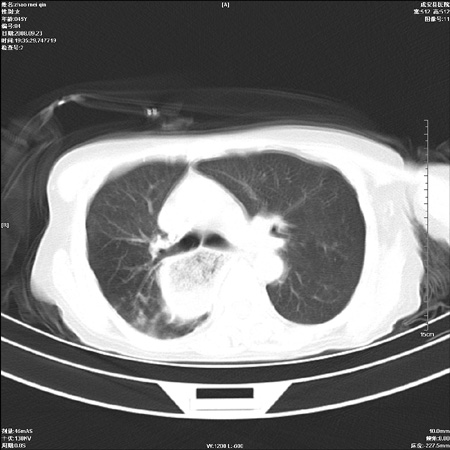

标题: CT15861:女 60 外伤后1小时 胸疼 [打印本页]

标题: CT15861:女 60 外伤后1小时 胸疼

外伤后1小时 胸疼 是外伤后引起的吗?

食道扩张明显下端逐渐变窄,倒像贲门失迟缓

食道ca术后胸腔胃,右肺挫伤?

非外伤性改变,典型的贲门失迟缓症

食道扩张明显下端逐渐变窄,大量食物存留,象贲门失迟缓症。